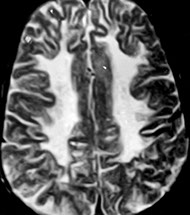

Central herniation - symmetrical downward displacement, most importantly of hypothalamic and thalamic structures, due to generalized and/or symmetrical swelling of both hemispheres (e.g. with massive bilateral cerebral swelling in severe anoxia). Damage to diencephalon causes stupor.

Cingulate herniation - also called subfalcial herniation, refers to the

lateral shift of cingulate gyrus across the midline ("midline shift")

under the free edge of the falx cerebri, as a result of a unilateral space occupying lesion.

Subfalcial herniation